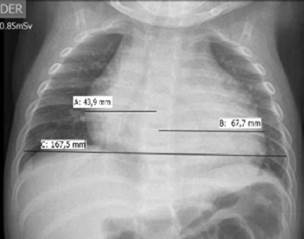

On admission, the patient presented: heart rate of 186 beats per minute; no hypotension (blood pressure at 106/65 mmHg); respiratory frequency of 50 breaths per minute; fever (38.3°C); SaO2 in 74% with oxygen at one liter per minute; mucocutaneous pallor; somnolence; no jugular vein engorgement; audible, rhythmic and tachycardic heart sounds; no pericardial rub, rhonchi and crepitus in both lungs; subcostal and suprasternal retractions; no hepatomegaly or edema; peripheral pulses and capillary refill without alterations, which required increased oxygen delivery (FIO2 0.5). His hemogram showed leukocytosis of 30 230mm3 with polymorphonuclear leukocytes of 24 360mm3, thrombocytosis (platelets of 1 006 000mm3); 5.8g/d serum proteins, and increase in acute phase reactants: C reactive protein of 96mg/L and procalcitonin of 5.24ng/ mL. Initial chest X-ray showed cardiomegaly, bibasilar and retrocardiac parenchymal opacities, without signs of pulmonary congestion or pleural effusion (Figure 1).

The initial chest X-ray showed bibasilar and retrocardiac consolidations. The cardio-thoracic index was 0.66 (>0.55) and was interpreted as cardiomegaly considering the patient's age. There was no evidence of pulmonary hyperflow or pulmonary venous congestion. The latter, together with electrocardiographic alterations (repolarization disorders compatible with acute pericarditis) and absence of signs of heart failure (no signs of systemic or pulmonary congestion or low cardiac output), led to rule out pericarditis and associated pericardial effusion, without cardiac tamponade at first. 3,12